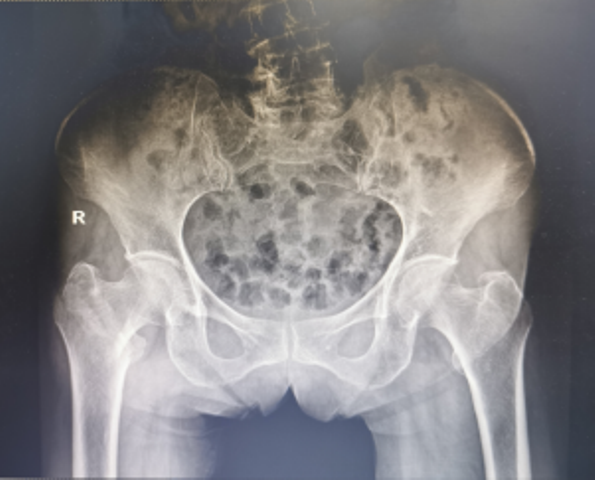

3月19日,91岁高龄的万奶奶在家行走的时候不慎摔倒在地,当即感到右髋部剧烈疼痛,且不能行走。家属赶紧拨打医院120急诊电话,随后收治骨一科治疗,经检查确诊:右股骨粗隆间粉碎性骨折。

然而万奶奶患有冠心病、腔隙性脑梗塞、贫血等老年基础病史,手术治疗非常棘手。